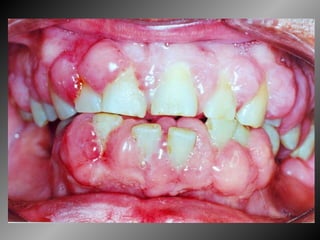

Concurso Público da Prefeitura Municipal de Curitiba Edital 03/2009 Qual é o tratamento apropriado para uma paciente de 15 anos com uma gengivite influenciada pelo uso de medicamento  Dilantin e que apresenta, além de aumento gengival, pseudobolsas periodontais e acúmulo exagerado de biofilme dental? A) Controle profissional do biofilme dental. B) Gengivectomia e osteoplastia. C) Cirurgia a retalho de Wildman modificado. D) Controle profissional do biofilme dental e gengivectomia. E) Gengivectomia.

Concurso Público daPrefeitura Municipal de Curitiba Edital 03/2009 Qual é o tratamento apropriado para uma paciente de 15 anos com uma gengivite influenciada pelo uso de medicamento Dilantin e que apresenta, além de aumento gengival, pseudobolsas periodontais e acúmulo exagerado de biofilme dental? A) Controle profissional do biofilme dental. B) Gengivectomia e osteoplastia. C) Cirurgia a retalho de Wildman modificado. D) Controle profissional do biofilme dental e gengivectomia. E) Gengivectomia.